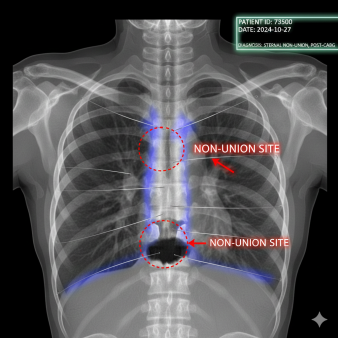

The challenge of diabetic bone healing is perhaps most visible in the aftermath of open-heart surgery. To access the heart, surgeons must saw through the sternum, later securing it with stainless steel wires. In a healthy recovery, these wires hold the bone steady until it fuses into a solid shield.

In diabetic patients, however, this process frequently fails. Radiologists often point to a "sternal gap" - a dark, empty space at the bottom of the chest bone where dense white matter should be. This "hole" is the hallmark of sternal dehiscence, a clinical separation that can cause an agonizing "clicking" or "grinding" sensation every time a patient breathes or moves.

The "big hole" or gap described in post-CABG (bypass) patients is a specific manifestation of these systemic failures.

Sternal Dehiscence This separation results in the "dark space" on imaging, where the lack of white opacity indicates a complete absence of new, calcified bone matter.